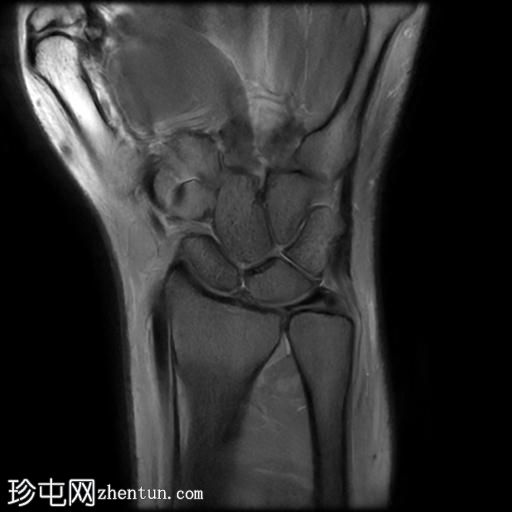

T2

冠状面

MRI显示腕部第一背侧肌腱(拇长展肌和拇短伸肌)增厚,并伴有异常增厚的实质内液体信号。腱鞘内液体增多。

尺侧腕伸肌腱可见异常线性实质内液体信号增多,与板状间质撕裂相关。

MRI表现和临床表现提示De Quervain腱鞘炎。